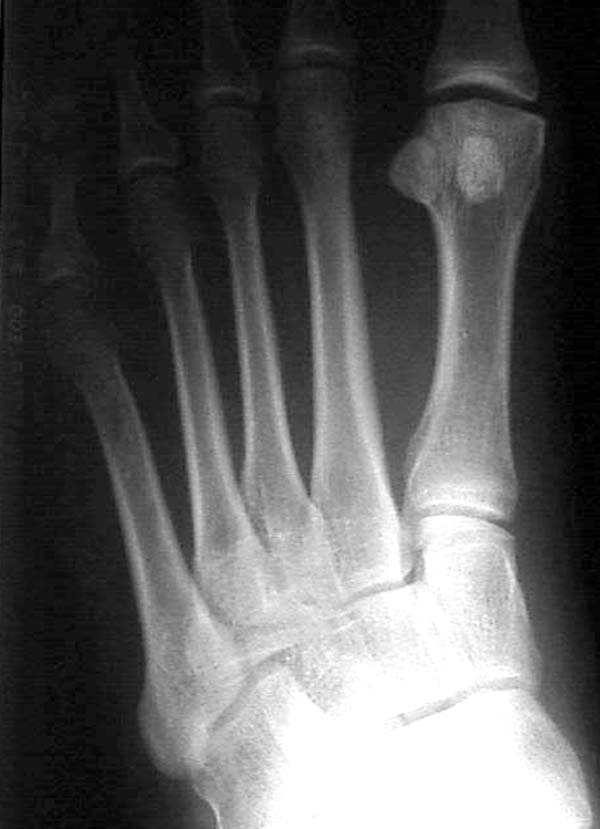

Имя     : Lt WB comparative.jpg

Тип     : image/jpeg

Размер  : 42489 байтов

Описание: отсутствует

Url     : http://weborto.net:8080/pipermail/ortho/attachments/20080320/e19da97a/attachment-0006.jpg